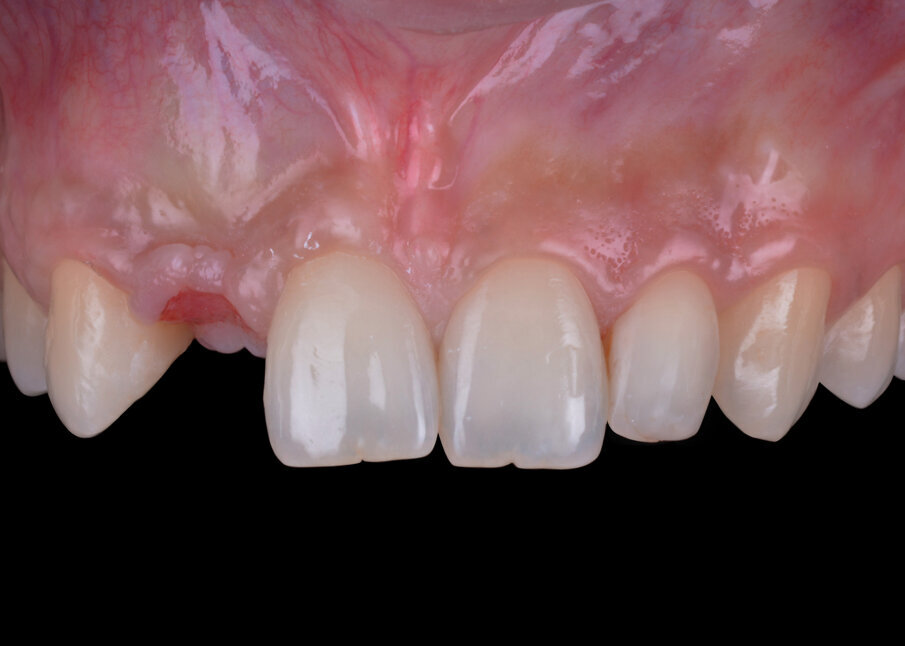

Con lo scopo di escludere controindicazioni assolute o relative alla terapia implantologica, lo studio del caso si basa sull’esame anamnestico. Nel caso specifico considerato di seguito, la paziente di anni 23 è classificabile nella categoria ASA I; all’esame obiettivo si evidenzia una mono-edentulia nel sito 1.2 a causa di un’agenesia trattata in passato con una terapia ortodontica di riallineamento dentario e di riapertura dello spazio protesico, spazio mantenuto con un Maryland bridge confezionato in resina acrilica. Un sondaggio parodontale della regione interessata permette di escludere lesioni parodontali ed evidenzia uno stato di buona salute dei tessuti duri e molli.

Gli esami radiografici completano l’approccio diagnostico iniziale e lo studio delle radiografie endorali del gruppo frontale, di un’ortopantomografia delle arcate dentarie e di una CBCT permettono di evidenziare un corretto allineamento radicolare degli elementi dentari contigui all’edentulia da trattare e una moderata atrofia orizzontale della cresta alveolare edentula (Fig. 1). Trattandosi di una riabilitazione del settore frontale è opportuno realizzare una dettagliata analisi estetica supportata da un esame fotografico corredato di fotografie extraorali (del volto e del sorriso), fotografie intraorali e da una ceratura diagnostica. L’attenzione iniziale è rivolta principalmente all’analisi dei tessuti molli e degli elementi dentari; in particolare, nel caso descritto, la paziente non presenta fattori estetici sfavorevoli dal momento che si riscontra la presenza di una linea del sorriso media, elementi dentari in area estetica sani e non discromici, fenotipo gengivale spesso, simmetria della festonatura gengivale e buona rappresentazione delle papille interdentali. Osservando in visione frontale la situazione clinica iniziale si evidenzia una lieve recidiva ortodontica dell’elemento 1.1 che si presenta leggermente mesializzato e vestibolarizzato rispetto alla sua posizione ideale (Fig. 2).

Fig. 2 - Situazione clinica iniziale (visione frontale).

Fig. 3 - Situazione clinica iniziale (visione laterale).